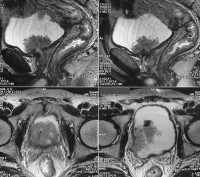

МРТ картина опухоли мочевого пузыря17.11.14